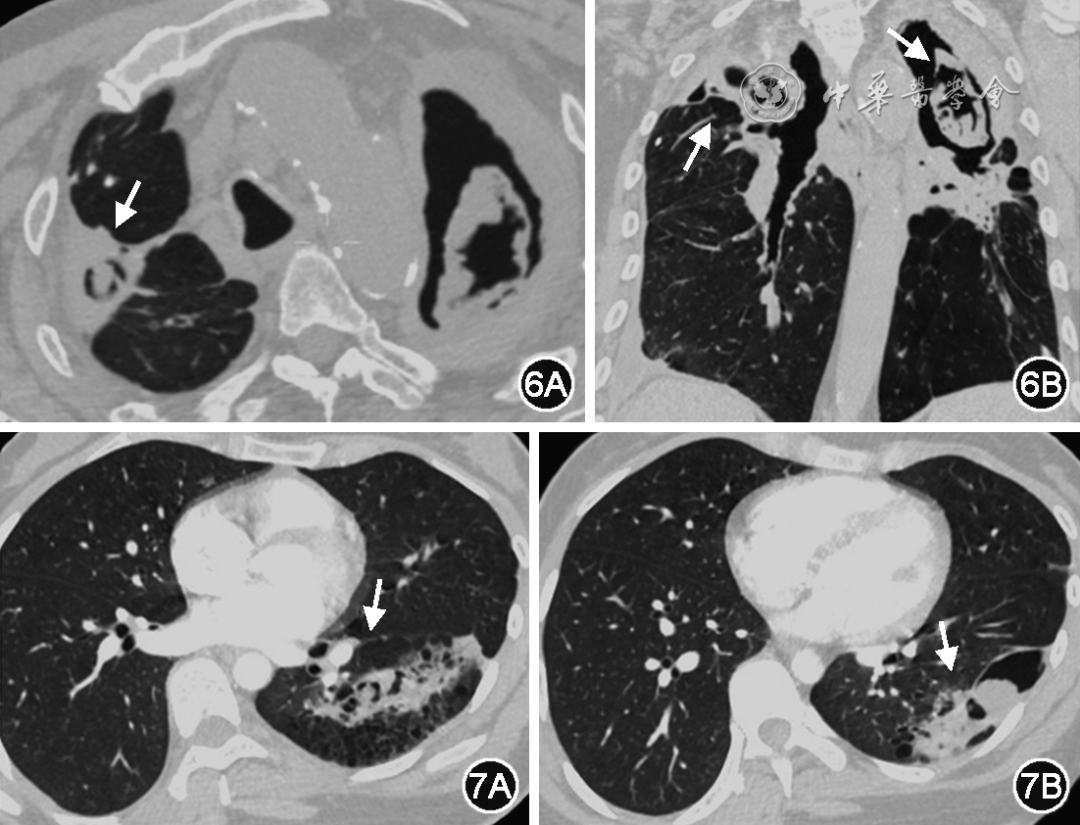

CCPA是慢阻肺合并CPA的最常见类型,在胸部CT上表现为多个或一个肺空洞/空腔结构,可含有一个或多个曲霉球或不规则内容物;常伴有临近胸膜的增厚。胸部影像可缓慢进展(图6)

图片

图6  CCPA典型表现。患者,男,64岁,慢阻肺和陈旧结核病史,咳嗽加重半年伴消瘦。双肺上叶可见多发不规则空洞,空洞内可见曲霉球形成(白箭头)。双肺可见肺气肿改变

图7  SAIA典型表现。患者,男性,50岁,慢阻肺病史,反复咳嗽、咳痰伴发热2个月余。胸部CT显示左肺下叶不规则空洞,空洞内见球样结构,空洞周围肺组织实变(白箭头)

当患者免疫功能受损加重时,CCPA可演进为SAIA。SAIA也被称为半侵袭性(semi-invasive)肺曲霉病或CNPA。尽管在分类上属于CPA,但SAIA在病程和临床表现方面更倾向于IPA,以亚急性或慢性咳嗽、咳痰以及发热等全身症状为特征。15%的SAIA患者出现咯血症状。SAIA的影像表现多样,包括空洞、结节、进展性实变伴空洞形成,空洞周围可伴有实变、小叶核心结节,临近胸膜可见增厚,增强扫描曲霉球或内容物不强化,空洞壁可见强化(图7)